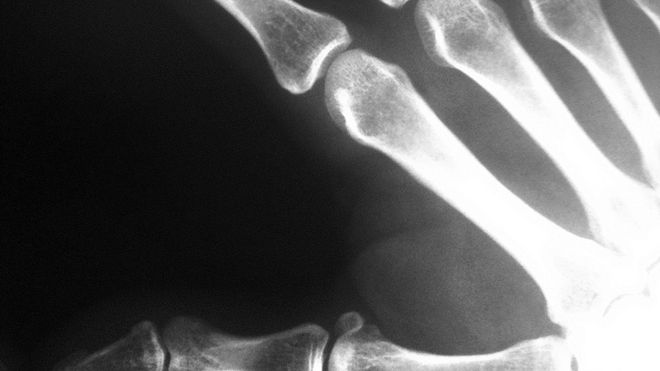

Nowa technologia opracowywana na University of Texas w Dallas może sprawić, że zdjęcia rentgenowskie będzie można wykonywać przy pomocy telefonu komórkowego.

Nowe podejście pozwala na tworzenie obrazów rentgenowskich przy pomocy fal elektromagnetycznych o częstotliwościach oscylujących wokół THz bez użycia dodatkowych soczewek lub lamp. Rozwój chipów CMOS (Complementary Metal-Oxide Semiconductor) oznacza także, że cały system obrazowania promieniowania rentgenowskiego można zmieścić w jednym tanim układzie. „Połączenie technologii CMOS i naszego systemu obrazowania oznacza, że można umieścić chip i odbiornik w telefonie, który zmieni się w kieszonkowe urządzenie do patrzenia przez ściany,”. mówi dr Kenneth O z University of Texas.

Zespół aktualnie pracuje nad skonstruowaniem w pełni funkcjonalnego modelu, który działać ma na „głębokość”. 4 cali. Po pierwsze prawdopodobnie jest to tańsze, po drugie naukowcy obawiają się, iż większy „zasięg” spowodowałby serię debat na temat prywatności. Pozwów również nie można by wykluczyć. Dla naukowców najważniejsze jest, by systemy obrazowania rentgenowskiego stały się tak tanie, by sprawdzenie, czy ta opuchlizna to tylko stłuczenie czy już złamanie, nie wymagało odsyłania pacjenta na radiologię. Tanie systemy obrazowania rentgenowskiego mogą także spowodować, że pojawią się gadżety do prześwietleń, o których nawet nam się nie śniło.